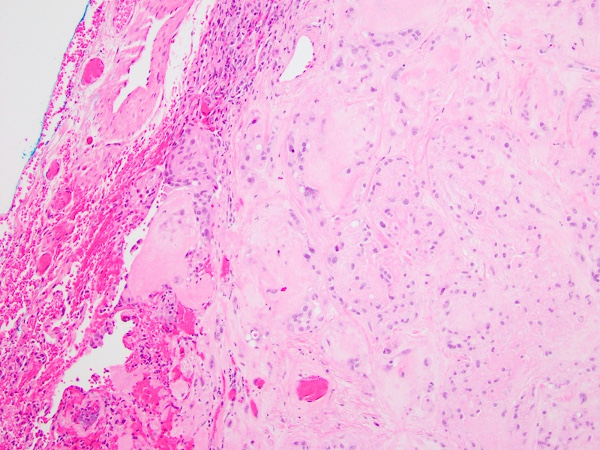

The patient underwent video-assisted thoracoscopic surgery of the right lower and upper lobes of lung. Gross examination of the resected specimen revealed two well-demarcated, intraparenchymal solid, round, white, firm tumors measuring 0.8 cm and 1.3 cm in greatest dimension. Microscopic examination revealed a well-circumscribed neoplasm composed of nests and cords of tumor cells within a myxohyaline stroma (Figure 1). The tumor cells had well-defined borders, abundant eosinophilic cytoplasm, and primarily round nuclei with open chromatin and conspicuous nucleoli (Figure 2). There were apparent cytoplasmic vacuoles in some of the neoplastic cells. No notable necrosis, mitotic activity, or nuclear pleomorphism was present.